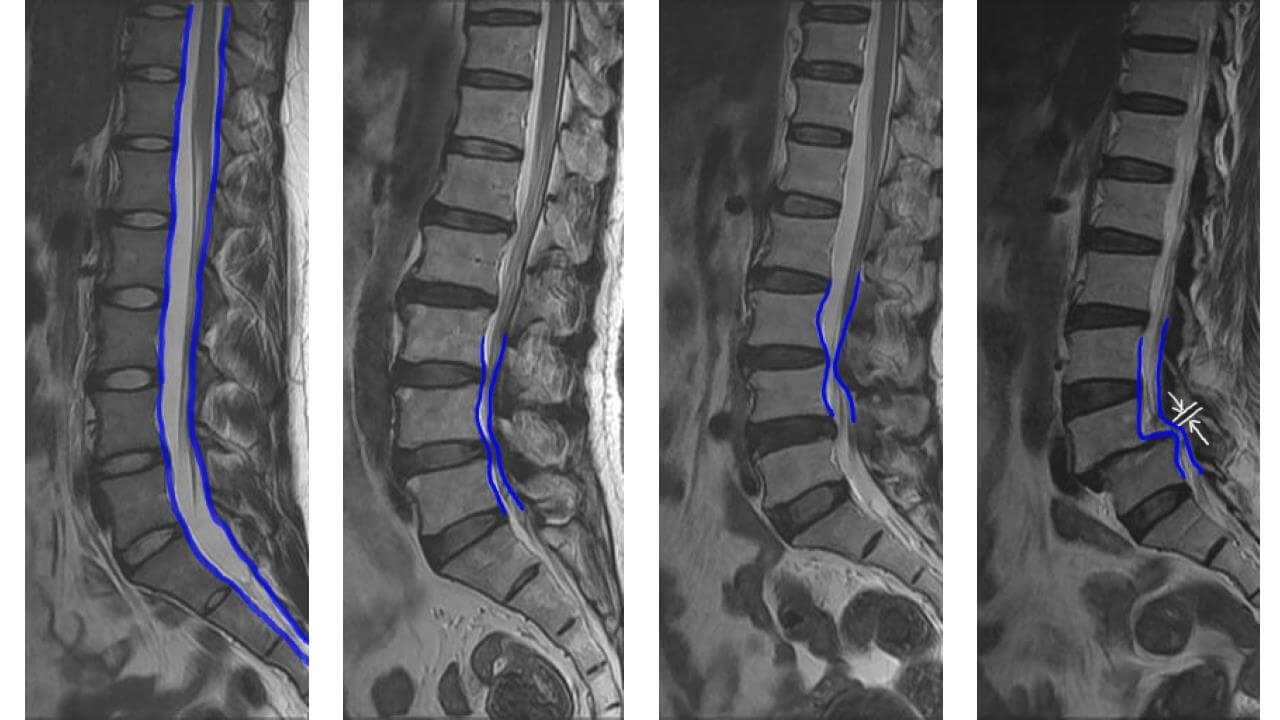

퇴행성 척추 협착증의 가장 흔한 원인은 척추의 퇴행성 고관절염으로, 이는 등의 관절 비대, 인대가 두꺼워지고 신경 경로를 좁히는 가시뼈 성장을 유발합니다. 척추 협착증은 종종 엉덩이나 항문 쪽으로 찌르는 듯한 통증과 타는 듯한 통증을 동반한 요통, 다리의 감각 장애, 근쇠약을 동반합니다. 취한 것이 좋습니다. 하지만 증상이 자주 나타나 심해지면 허리를 굽히거나 걸음을 멈추고 앉아서 쉬면 사라지던 증상이 다시 나타날 수 있습니다. 이러한 증상을 신경성 간헐적 파행이라고 하며, 협착 정도에 따라 걷는 거리가 짧아집니다.